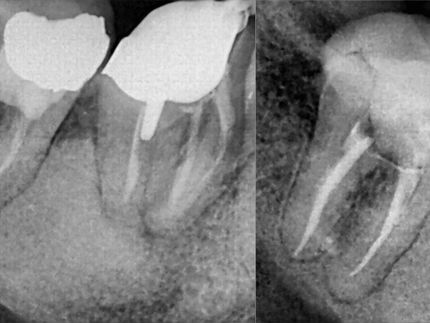

Endodontic treatment aims to repair and save a badly damaged infected tooth. the procedure involves removing the damaged pulp or nerve, cleaning disinfecting it, and then filling and sealing it.

The following cases were done using MTWO rotary endodontic instruments by VDW for fast and safe root canal preparation.